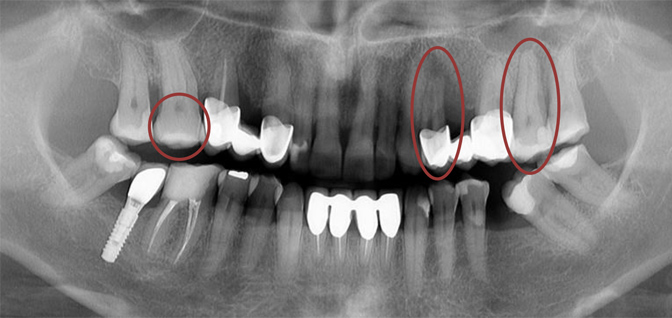

Nello Studio dentistico Jindra-Strika TAC principalmente si usa per la terapia implantare e nei casi in cui non è possibile determinare con precisione la condizione dei denti. Esso fornisce un lavoro professionale, con qualità e successo trattare i nostri pazienti. In seguito vogliamo spiegare i benefici della TAC.